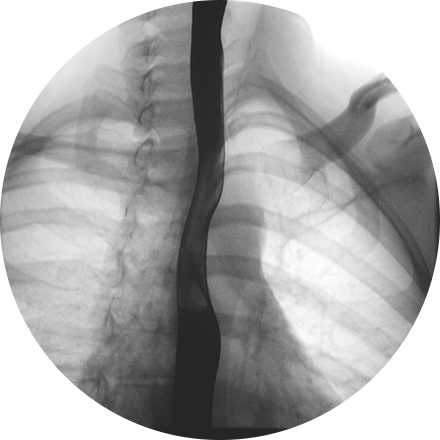

Angiogram

An angiogram is an X-ray exam of the arteries and veins to diagnose blockages and other blood vessel problems. It can reveal the integrity of the cardiovascular system in specific areas throughout the body. Combined with the use of intravenous contrast medium injected via a catheter, an angiogram identifies areas of blockage or damaged vessels within the circulatory system. CT and MRI may also be used to gain additional images of the arteries.